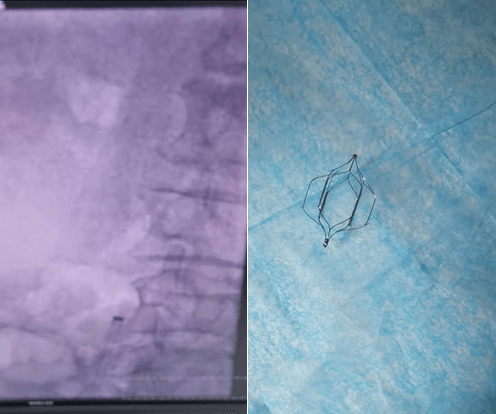

經(jīng)治療后患者病情好轉(zhuǎn),但復(fù)查深靜脈彩超仍有游離血栓,崔主任指示:該患者再次肺血栓栓塞可能較大,有可能危及患者生命,時(shí)間刻不容緩!在取得了患者及家屬的知情同意后,安排了下腔靜脈造影術(shù)+下腔靜脈濾器植入術(shù)。

術(shù)后繼續(xù)積極治療,再未出現(xiàn)過暈厥的情況,入院時(shí)的癥狀均得到了改善,嚴(yán)密監(jiān)測(cè)了患者下肢靜脈血栓,在治療1周后復(fù)查超聲檢查提示下肢深靜脈新鮮血栓的影子已經(jīng)消失。傳統(tǒng)的治療方案到此已經(jīng)獲得了滿意的療效。但崔主任從患者長(zhǎng)期預(yù)后的角度考慮,濾器遺留在血管里,存在其他不可預(yù)知的風(fēng)險(xiǎn),并需要長(zhǎng)期口服抗凝藥物預(yù)防血栓的形成,這樣也增加了消化道、眼底、腦血管等出血的風(fēng)險(xiǎn)。于是崔主任帶領(lǐng)團(tuán)隊(duì),為患者實(shí)施了經(jīng)皮深靜脈濾器取出術(shù),極大的避免了不良事件發(fā)生的機(jī)率。

肺栓塞發(fā)病率較高,病死率亦很高,由于肺栓塞癥狀缺乏特異性,確診需要特殊的檢查技術(shù),即便是發(fā)達(dá)國(guó)家,每年因肺栓塞死亡的人口超過29萬(wàn)。下肢深靜脈血栓是造成肺栓塞的常見血栓來源部位,常常發(fā)生于創(chuàng)傷/骨折、外科手術(shù)后、腦卒中、吸煙、長(zhǎng)期制動(dòng)、高齡、肥胖等具備以上危險(xiǎn)因素的人群,脫落的血栓游行至肺動(dòng)脈造成栓塞的同時(shí)嚴(yán)重影響了肺的氣體血液交換,導(dǎo)致低氧血癥,亦使肺動(dòng)脈的血循環(huán)障礙,嚴(yán)重者發(fā)生低血壓,甚至造成暈厥,崔旭輝主任團(tuán)隊(duì)及時(shí)洞察病情,實(shí)施就治,利用下腔靜脈濾器這把小“傘”,為患者的生命撐起了一片天。